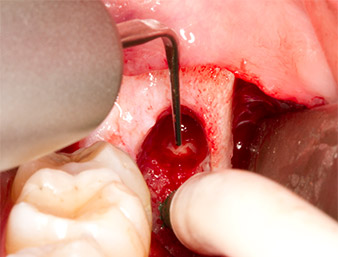

À l'aide d’un insert pour le débridement parodontal (Piezomed P1), l’espace ligamentaire parodontal de la racine résiduelle est ensuite élargi de manière minimale (Fig. 8).

Le même insert activé est inséré dans le canal radiculaire et détache le fragment sous l’effet de ses vibrations à micro-oscillations (Fig. 9, 10).

Piezomed P1

Fig. 9 : L’insert Piezomed P1 est recommandé par le fabricant essentiellement pour le débridement parodontal mais il est également adapté à la chirurgie. Ici, il est placé dans le canal radiculaire après élargissement minimal de l’espace ligamentaire parodontal.

Fig. 10 : Grâce à sa forme très affinée, l'insert peut pénétrer dans le canal radiculaire et extraire le reste radiculaire sous l’effet des micro-oscillations (vibrations).

Il est ensuite possible, grâce à l’insert P1, d’extraire en un seul geste le reste radiculaire d’environ six millimètres de long (Fig. 11).